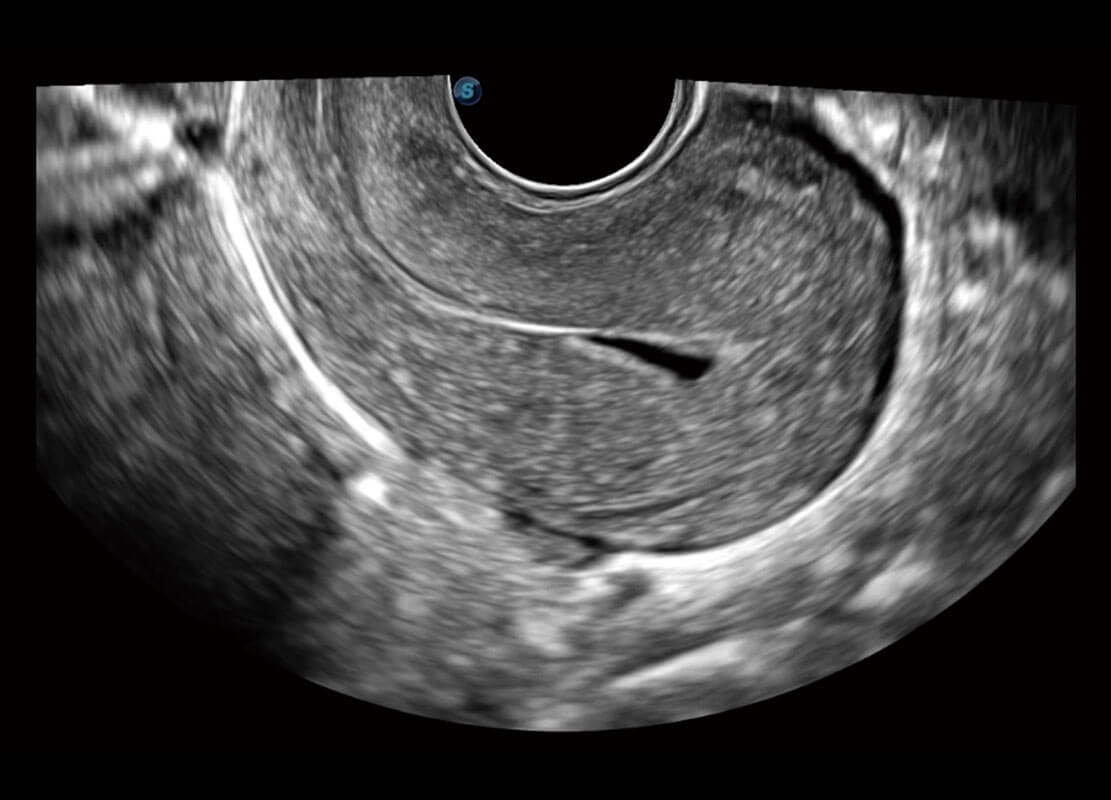

生殖健康

P60优异的图像质量搭载专科探头,在妇科基础疾病的诊断、卵泡生长的监测、输卵管通畅情况的判别等方面为您提供生殖应用方案。

• 腔内妇科-宫腔分离

• 腔内妇科-卵巢

• 腔内三维-宫内节育器

• 腔内三维-光影成像